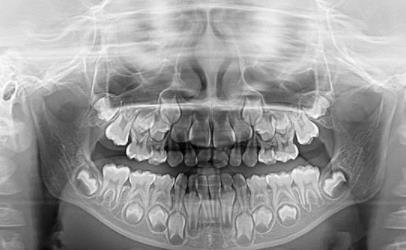

第三張拍片圖片如下:

這張就是在換牙時期,口內(nei) 既有乳牙也有恒牙的片子,是比較混亂(luan) 的,如果不拍片子確定口內(nei) 牙齒的基本生長狀態,以及畸形的情況,是沒有辦法進行矯治的,而這些複雜的牙齒情況是肉眼看不出來的。